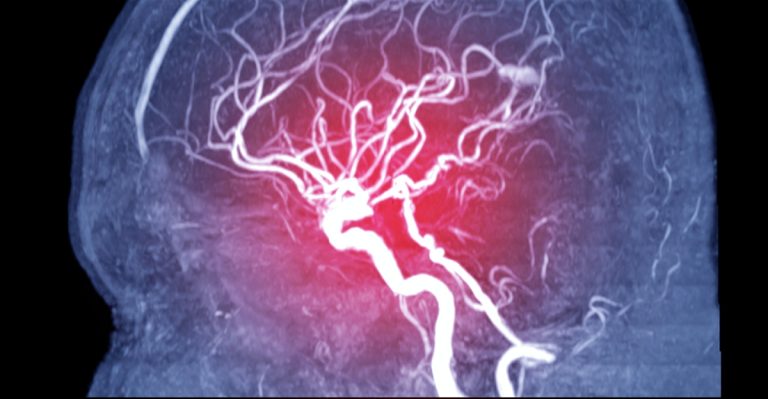

i Zdroj fotografie: iStock